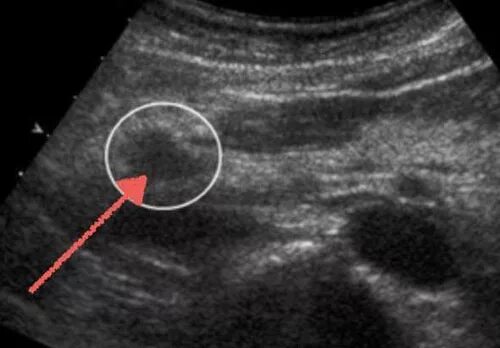

Повышенной эхогенности неоднородной структуры